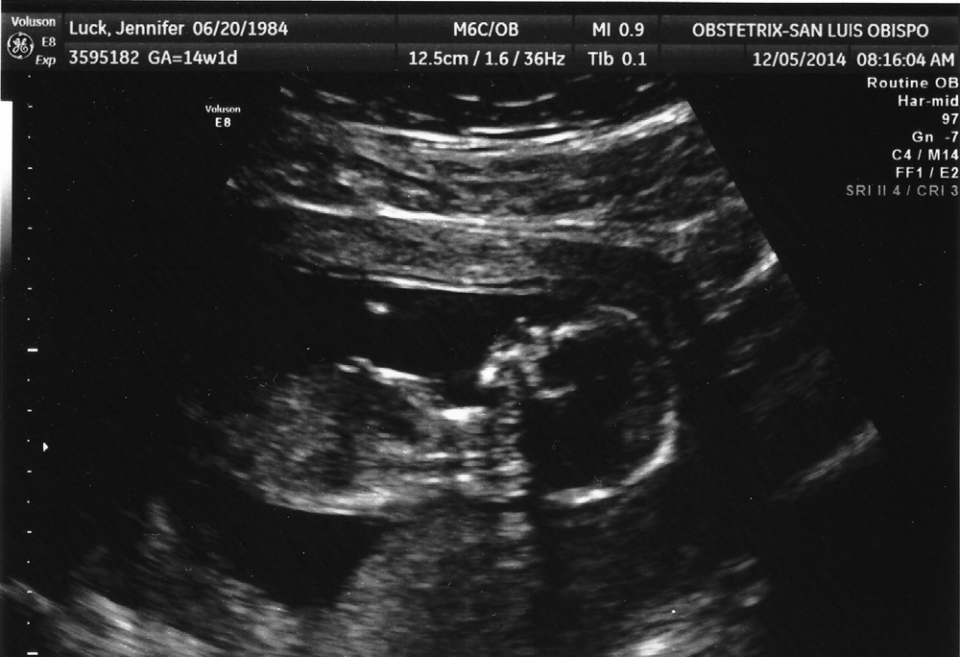

First picture of Baby Wolfe! Our 15-week ultrasound.

Baby is 14 weeks and one day.

Taken 12/15/2014